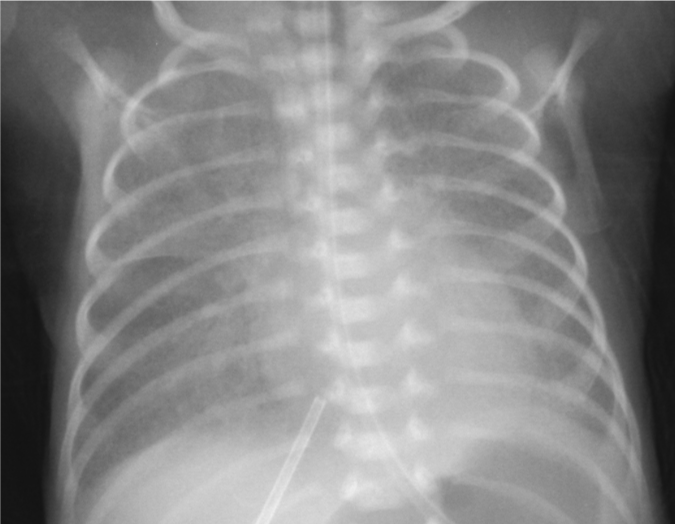

A 10-minute-old neonate is evaluated in the delivery room for low oxygen saturation and difficulty breathing.  The patient was born at 36 weeks gestation to a 37-year-old mother whose pregnancy was complicated by poorly controlled type 2 diabetes mellitus.  Membranes were ruptured 3 hours prior to delivery, and the fluid was clear.  Apgar scores were 5 and 7 at 1 and 5 minutes, respectively.  Temperature is 36.9 C (98.4 F) , pulse is 166/min, and respirations are 70/min.  Examination shows cyanosis of the lips and mucous membranes.  The patient is grunting and has intercostal and subcostal retractions.  Cardiac examination shows a 1/6 systolic ejection murmur at the left upper sternal border.  Breath sounds are decreased bilaterally.  The abdomen is soft with no organomegaly.  Pulses are 2+ in all extremities.  Pulse oximetry on room air is 64% in the right hand and foot.  An orogastric tube is placed, and the patient is started on continuous positive airway pressure with supplemental oxygen.  Pulse oximetry improves to 82%.  Chest radiograph is shown in the image below: A 10-minute-old neonate is evaluated in the delivery room for low oxygen saturation and difficulty breathing.  The patient was born at 36 weeks gestation to a 37-year-old mother whose pregnancy was complicated by poorly controlled type 2 diabetes mellitus.  Membranes were ruptured 3 hours prior to delivery, and the fluid was clear.  Apgar scores were 5 and 7 at 1 and 5 minutes, respectively.  Temperature is 36.9 C (98.4 F) , pulse is 166/min, and respirations are 70/min.  Examination shows cyanosis of the lips and mucous membranes.  The patient is grunting and has intercostal and subcostal retractions.  Cardiac examination shows a 1/6 systolic ejection murmur at the left upper sternal border.  Breath sounds are decreased bilaterally.  The abdomen is soft with no organomegaly.  Pulses are 2+ in all extremities.  Pulse oximetry on room air is 64% in the right hand and foot.  An orogastric tube is placed, and the patient is started on continuous positive airway pressure with supplemental oxygen.  Pulse oximetry improves to 82%.  Chest radiograph is shown in the image below:   Blood cultures are obtained, and intravenous antibiotics are started.  Which of the following is the most appropriate pharmacotherapy for this patient? A) Corticosteroids B) Indomethacin C) Nitric oxide D) Prostaglandin E) Surfactant Blood cultures are obtained, and intravenous antibiotics are started.  Which of the following is the most appropriate pharmacotherapy for this patient?